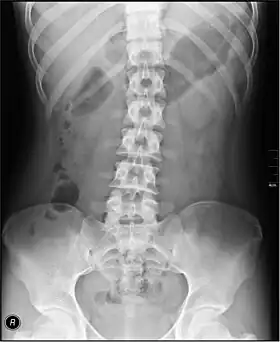

In children, abdominal radiography is indicated in the acute setting in suspected bowel obstruction, gastrointestinal perforation, foreign body in the alimentary tract, suspected abdominal mass and intussusception (latter as part of the differential diagnosis).[13] Yet, CT scan is the best alternative for diagnosing intra-abdominal injury in children.[13] For acute abdominal pain in adults, an abdominal X-ray has a low sensitivity and accuracy in general. Computed tomography provides an overall better surgical strategy planning, and possibly less unnecessary laparotomies. Abdominal X-ray is therefore not recommended for adults presenting in the emergency department with acute abdominal pain.[14]

The standard abdominal X-ray protocol is usually a single anteroposterior projection in supine position.[15] A Kidneys, Ureters, and Bladder projection (KUB) is an anteroposterior abdominal projection that covers the levels of the urinary system, but does not necessarily include the diaphragm.

- Lumbar Spine - AP and Lateral +/- L5/S1 view in the UK, with obliques and Flexion and Extension requests being rare.[15] In the US, basic projections include an AP, two Obliques, a Lateral, and a Lateral L5-S1 spot to better visualize the L5-S1 interspace. Special projections are AP Right and Left bending, and Laterals with Flexion and Extension.